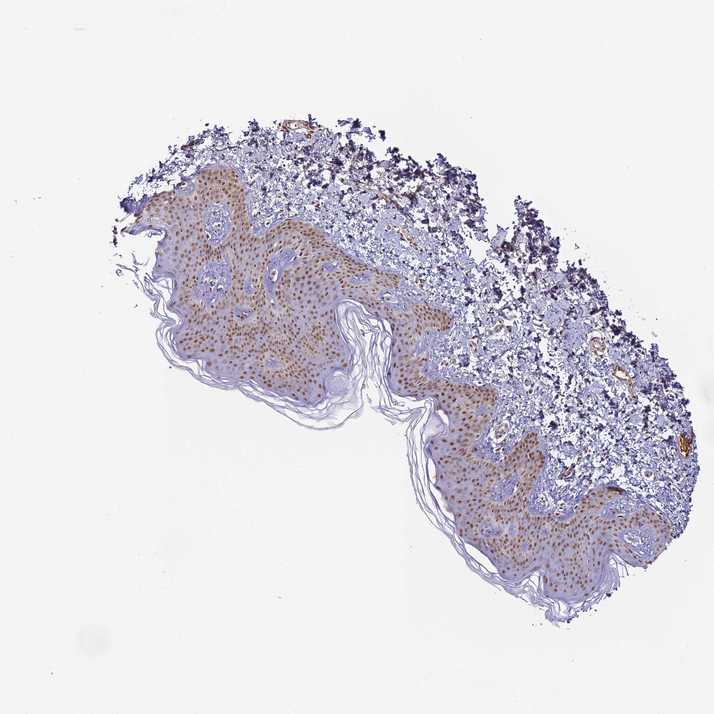

SKIN 1 - Antibody stainingi

Antibody staining in the annotated cell types in the current human tissue is reported as not detected, low, medium, or high, based on conventional immunohistochemistry profiling in selected tissues. This score is based on the combination of the staining intensity and fraction of stained cells.

Each image is clickable and will lead to virtual microscopy that enables deeper exploration of all samples and also displays staining intensity scores, fraction scores and subcellular localization as well as patient and tissue information for each sample.

Antibody HPA043258Antibody HPA043621

Langerhans MediumMedium

Fibroblasts MediumMedium

Keratinocytes MediumMedium

Melanocytes MediumMedium